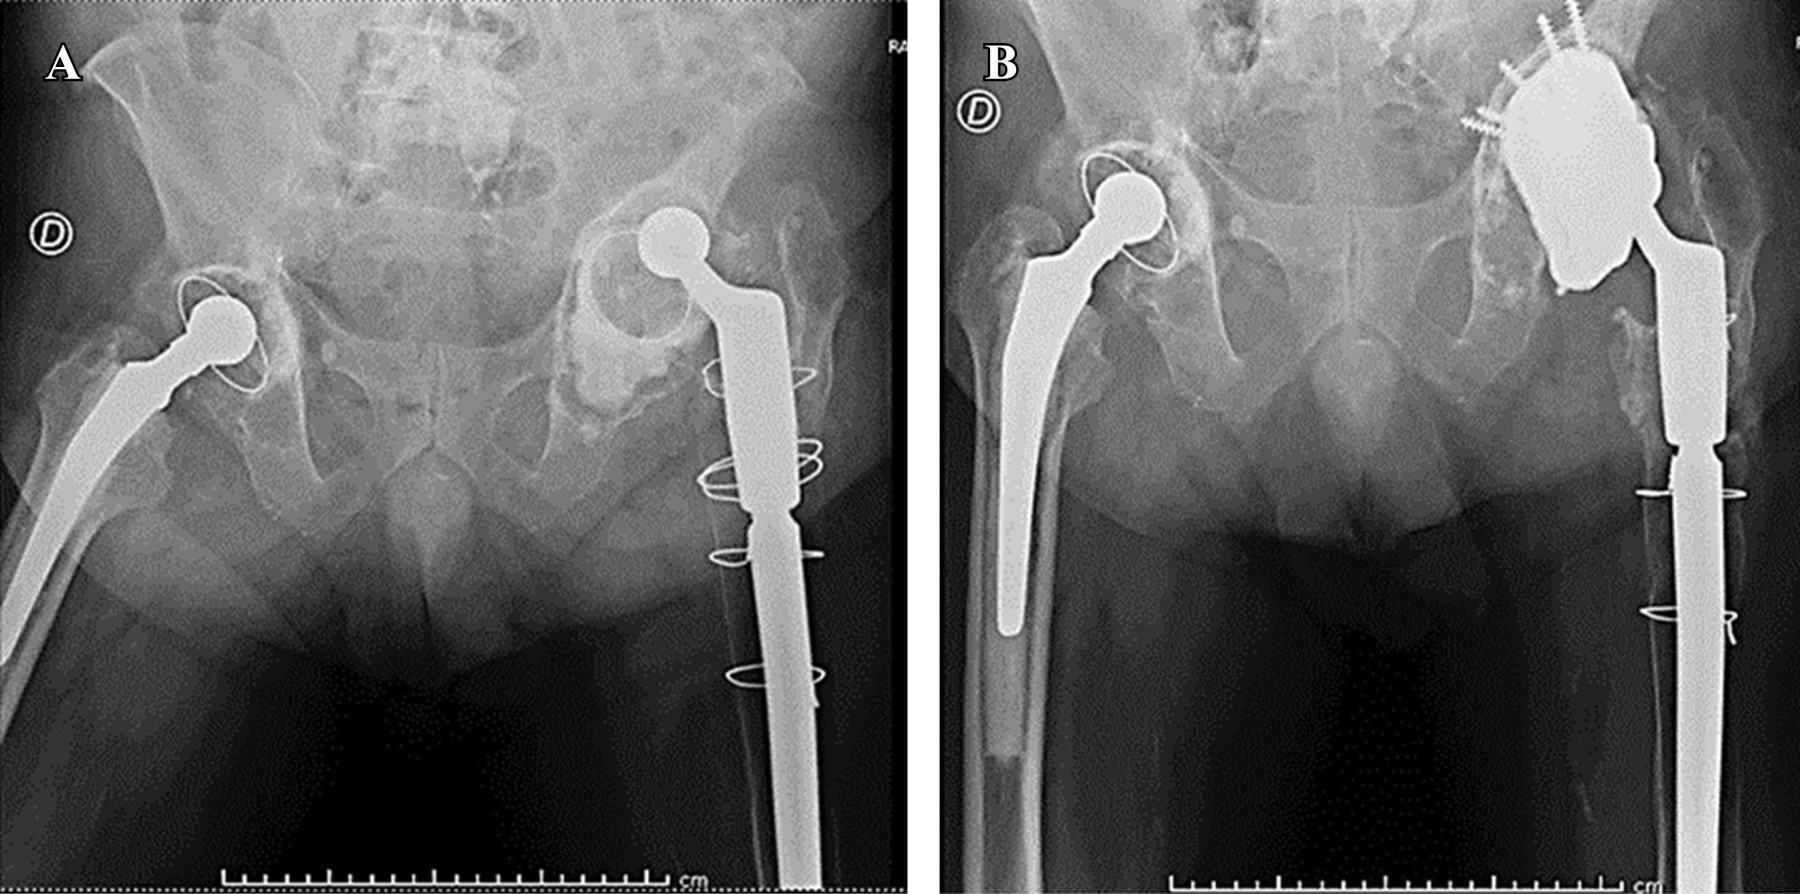

La reimplantación de los componentes cementados y no cementados se llevó a cabo en una y dos etapas, respectivamente (como se resume en la Tabla 2). Se conservaron tanto el componente acetabular como el femoral (Figuras 1 y 2).

Figura 1